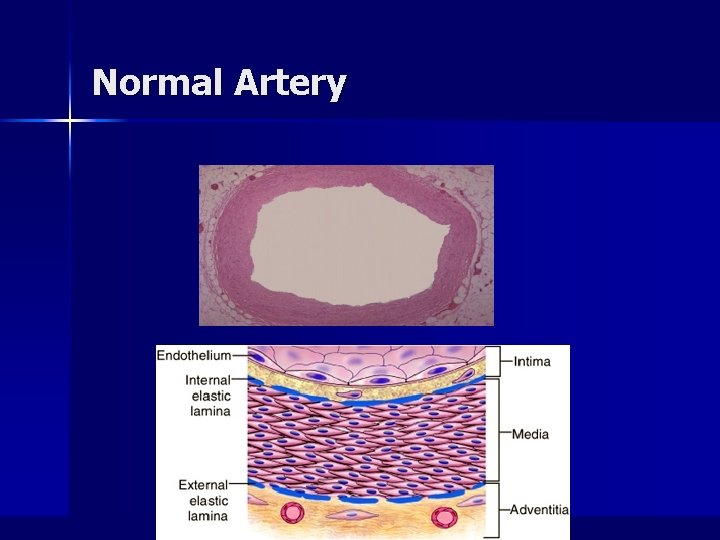

General Comments n Arteriosclerosis – Thickening and loss of elasticity of arterial walls – Hardening of the arteries – Greatest morbidity and mortality of all human diseases n Two major processes in plaque formation: – Intimal thickening – Lipid accumulation

Normal Artery

Summary of Atherosclerotic Process n n n n n Multifactorial process (risk factors) Initiated by endothelial dysfunction Up regulation of endothelial and leukocyte adhesion molecules Macrophage diapedesis LDL transcytosis LDL oxidation Foam cells Recruitment and proliferation of smooth muscle cells (synthesis of connective tissue proteins) Formation and organization of arterial thrombi